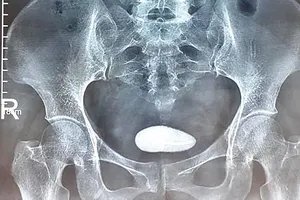

Phẫu thuật nội soi thành công trường hợp thai ngoài tử cung bị sảy vào ổ bụng Y tế - Sức khỏe 09/08/2018 14:15